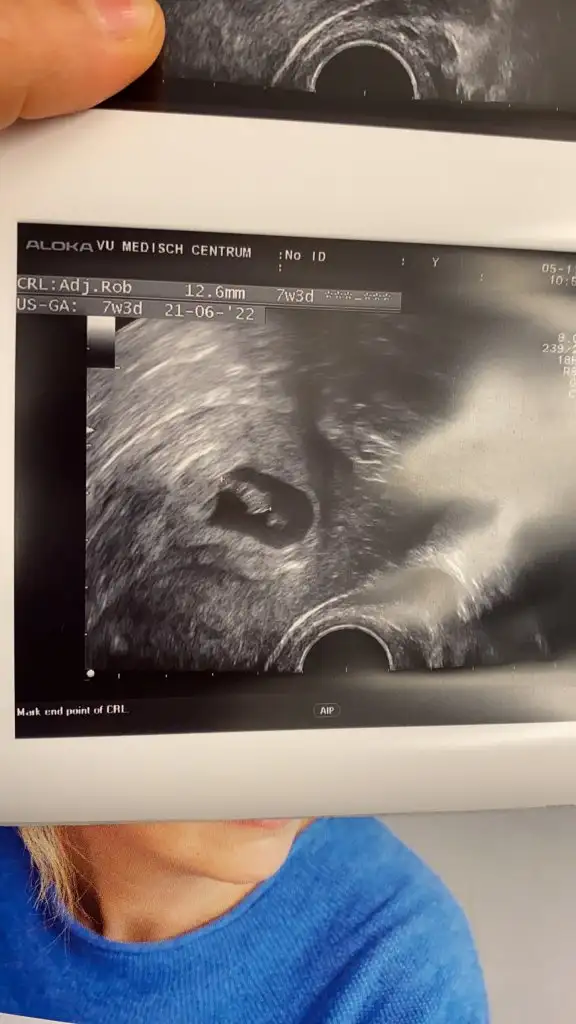

Kızlar bu arada cinsiyet tahmini yapabilen var mı aranız da

Genel de tutuyor tahminlerim şansımı denerim ultrason resmini gönderirsen

Bunlar yakından foto uzaktan altta olan kısım yok gibi görünüşe göre erkeğe benziyor tabi bu kese durumuna bakarak tahmin ediyorum.Nub teorisi için de -12. Haftalarda gidersen ona göre de yorum yaparım.Allah gönlünde kini saglikcakla.nasip.etsin inşallahBi bak canım

Nasıl kız. Kesenin şekline göre belli oluyor mu Ayy bende merak ettimBunlar yakından foto uzaktan altta olan kısım yok gibi görünüşe göre erkeğe benziyor tabi bu kese durumuna bakarak tahmin ediyorum.Nub teorisi için de -12. Haftalarda gidersen ona göre de yorum yaparım.Allah gönlünde kini saglikcakla.nasip.etsin inşallah![]()